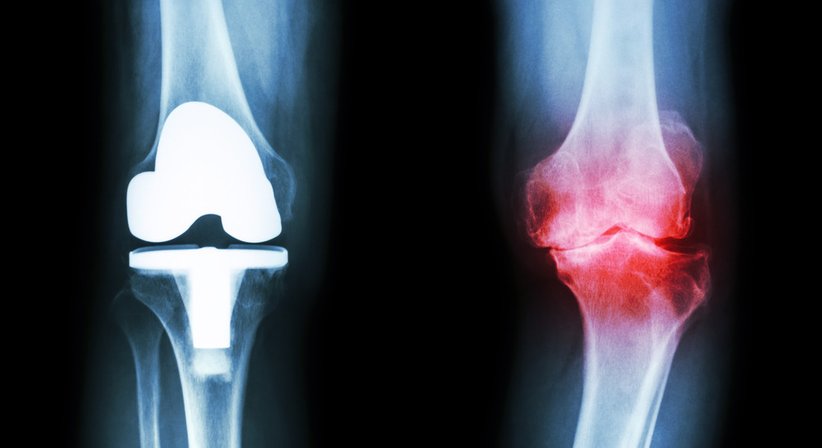

Eine Knieprothese bzw. ein künstliches Kniegelenk ist dann indiziert, wenn das eigene Knie verschlissen und abgenutzt ist. In über 90% der Fälle ist eine schwere Kniegelenksarthrose (Gonarthrose) der Grund für den Einsatz des künstlichen Gelenks.

Bei einer sogenannten Knie-TEP wird das gesamte Gelenk durch spezielle Oberflächenimplantate ersetzt. Der häufigste Grund einer Knietotalendoprothese ist der komplette Verlust des Gelenkknorpels.